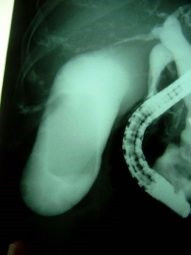

Colelitiasis y coledocolitiasis ERCP

Envíado por Dr. Carlos Miguel Zavaleta Consuegra